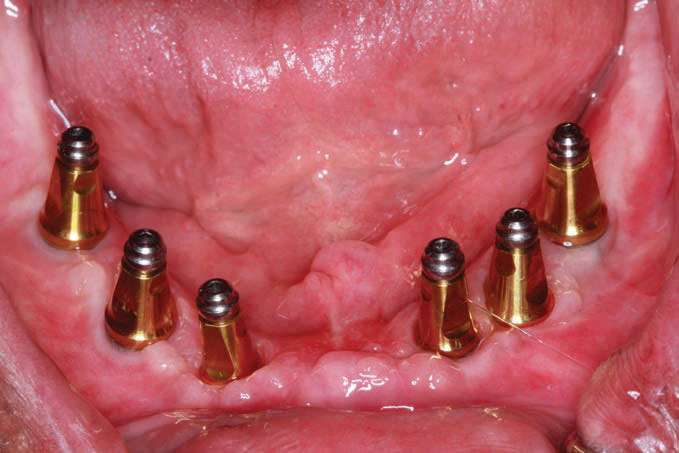

The BioHorizons implants were placed with a good A-P spread, and the bone in the anterior mandible was left in case it was needed at the uncovery appointment (Figure 8). At the uncovery visit, the LightScalpel laser was used to perform a trephine of the posterior implants by placing the surgical guide, marking the osteotomy sites with a Dr. Thompson’s marking stick, and (using a super-pulsed 2W setting) to gently remove the cuff of tissue over the implants (Figure 9). In the anterior mandible, a full-thickness flap was done, and the remaining bone was removed with the PIEZOSURGERY device (Figure 10). The peri-mucosal healing abutments were placed, and a soft-tissue conditioner was placed in the lower denture (Figure 11). After one month of healing, the patient was ready for impressions (Figure 12).

The 3-in-1 abutments are included with the Tapered Internal Dental Implants (BioHorizons) and, when a ball-top screw is placed, these become impression copings (Figure 13a). The initial ball-top screw impression was taken (Aquasil Ultra Xtra Plus [Dentsply Sirona Restorative]) (Figure 13b). This impression material has excellent wettability and tear strength for capturing the subgingival abutment implant interface. The setting time of 5.5 minutes gives adequate working time and is appropriate for larger cases for which an extended working time is desirable.